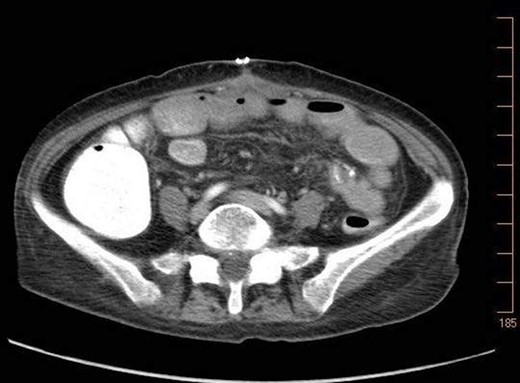

On 7.8.18 the patient had return of bowel function complicated by blood per rectum and an episode of bloody emesis with drop in Hgb 9 > 7.0. The patient received 2 units PRBCs. GI consulted deemed blood per rectum likely from bleeding from anastomoses line. 7.8 Zosyn began for 7 days. Due to the concern for potential bleed, on 7.9 the patient had CTAP (Fig. 5) which demonstrated newly developed pneumatosis within ascending and transverse colon. Pt at this time had appropriate post-surgical abdominal pain, no leukocytosis 4.6, and was HDS. Decision was made to conservatively manage this form of colonic pneumatosis, with TPN, antibiotics, and bowel rest. 7.11 EGD revealed a 5 mm ulcer at duodenal bulb. CTAP (Fig. 6) on 7.14.18 demonstrated largely resolved pneumatosis of ascending and transverse colon. 7.17 Mechanical soft diet, discharged home.

7.9.18: CTAP w/IV and PO contrast: pneumatosis within ascending and transverse colon, no evidence of bowel thickening or fat stranding, no evidence of bowel obstruction.